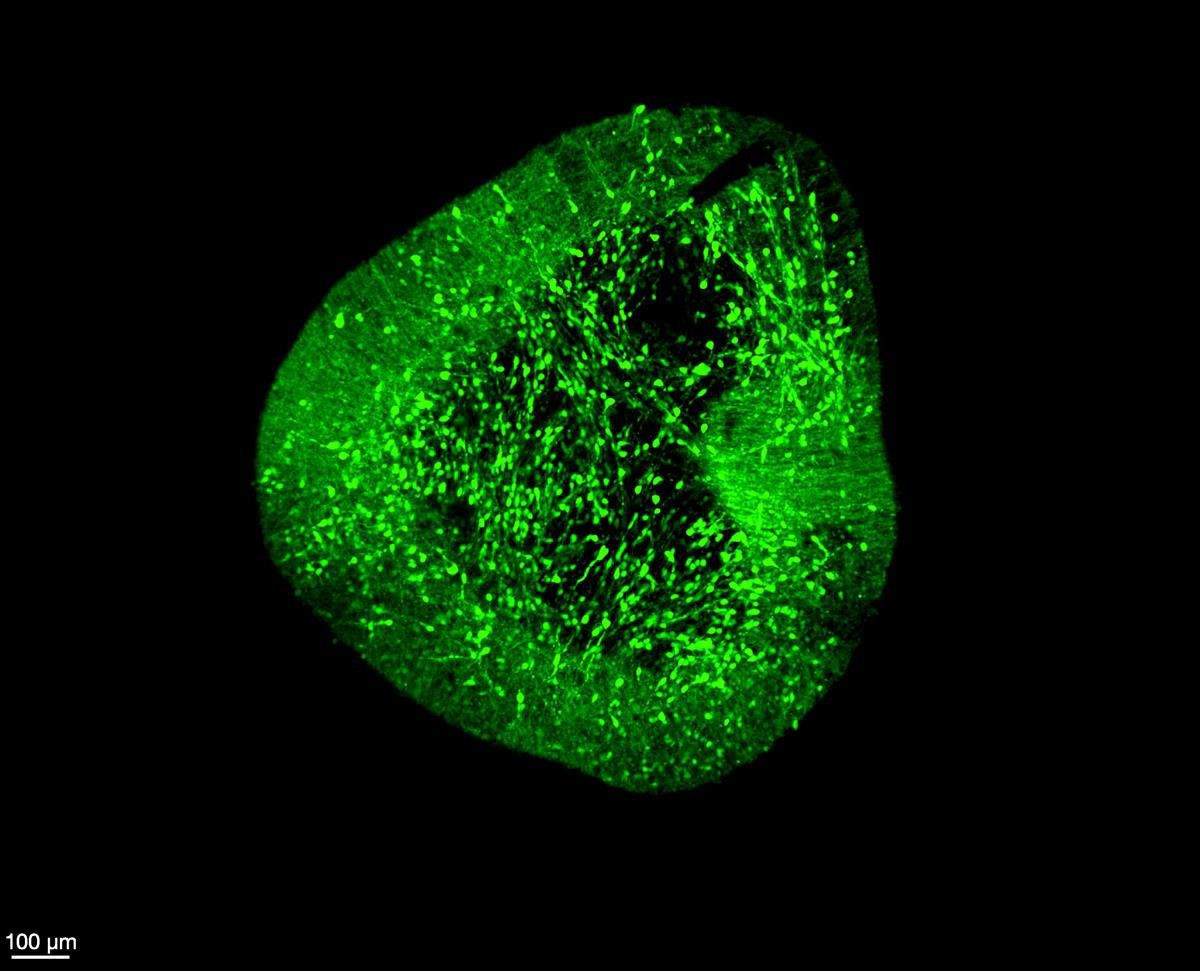

Μια ερευνητική ομάδα από το Duke-NUS Medical School παρουσίασε έναν πρωτοποριακό χάρτη του ανθρώπινου εγκεφάλου, ικανό να αποκαλύψει πώς σχηματίζονται...